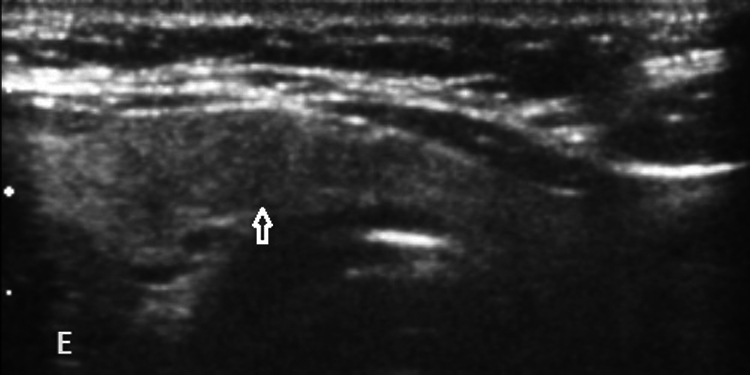

We present a case of a woman treated for breast carcinoma (BCA) found to have a benign hyperfunctioning nodular goiter, its likely transformation to MTC, and its treatment. Family history revealed papillary thyroid cancer in her nephew.